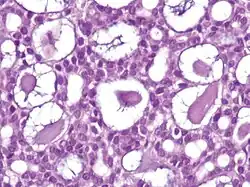

| Cystic basal-cell carcinoma | Morphologically characterized by dome-shaped, blue-gray cystic nodules.[31]: 647 |

| |